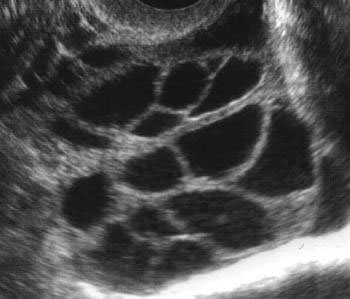

Los dolores abdominales despúes de una transferencia embrionaria en una fecundación in vitro pueden deberse a motivos diferentes. Por un lado, símplemente por la transferencia, se pueden producir contracciones uterinas que se pueden identificar como dolor abdominal. También se debe considerar la posibilidad de un síndrome de hiperestimulación ovárica si el número de óvulos obtenido fue elevado y existe distensión abdominal. En cualquiera de los casos es importante consultar en el centro de reproducción asisitida en el caso de que estos dolores sean importantes.